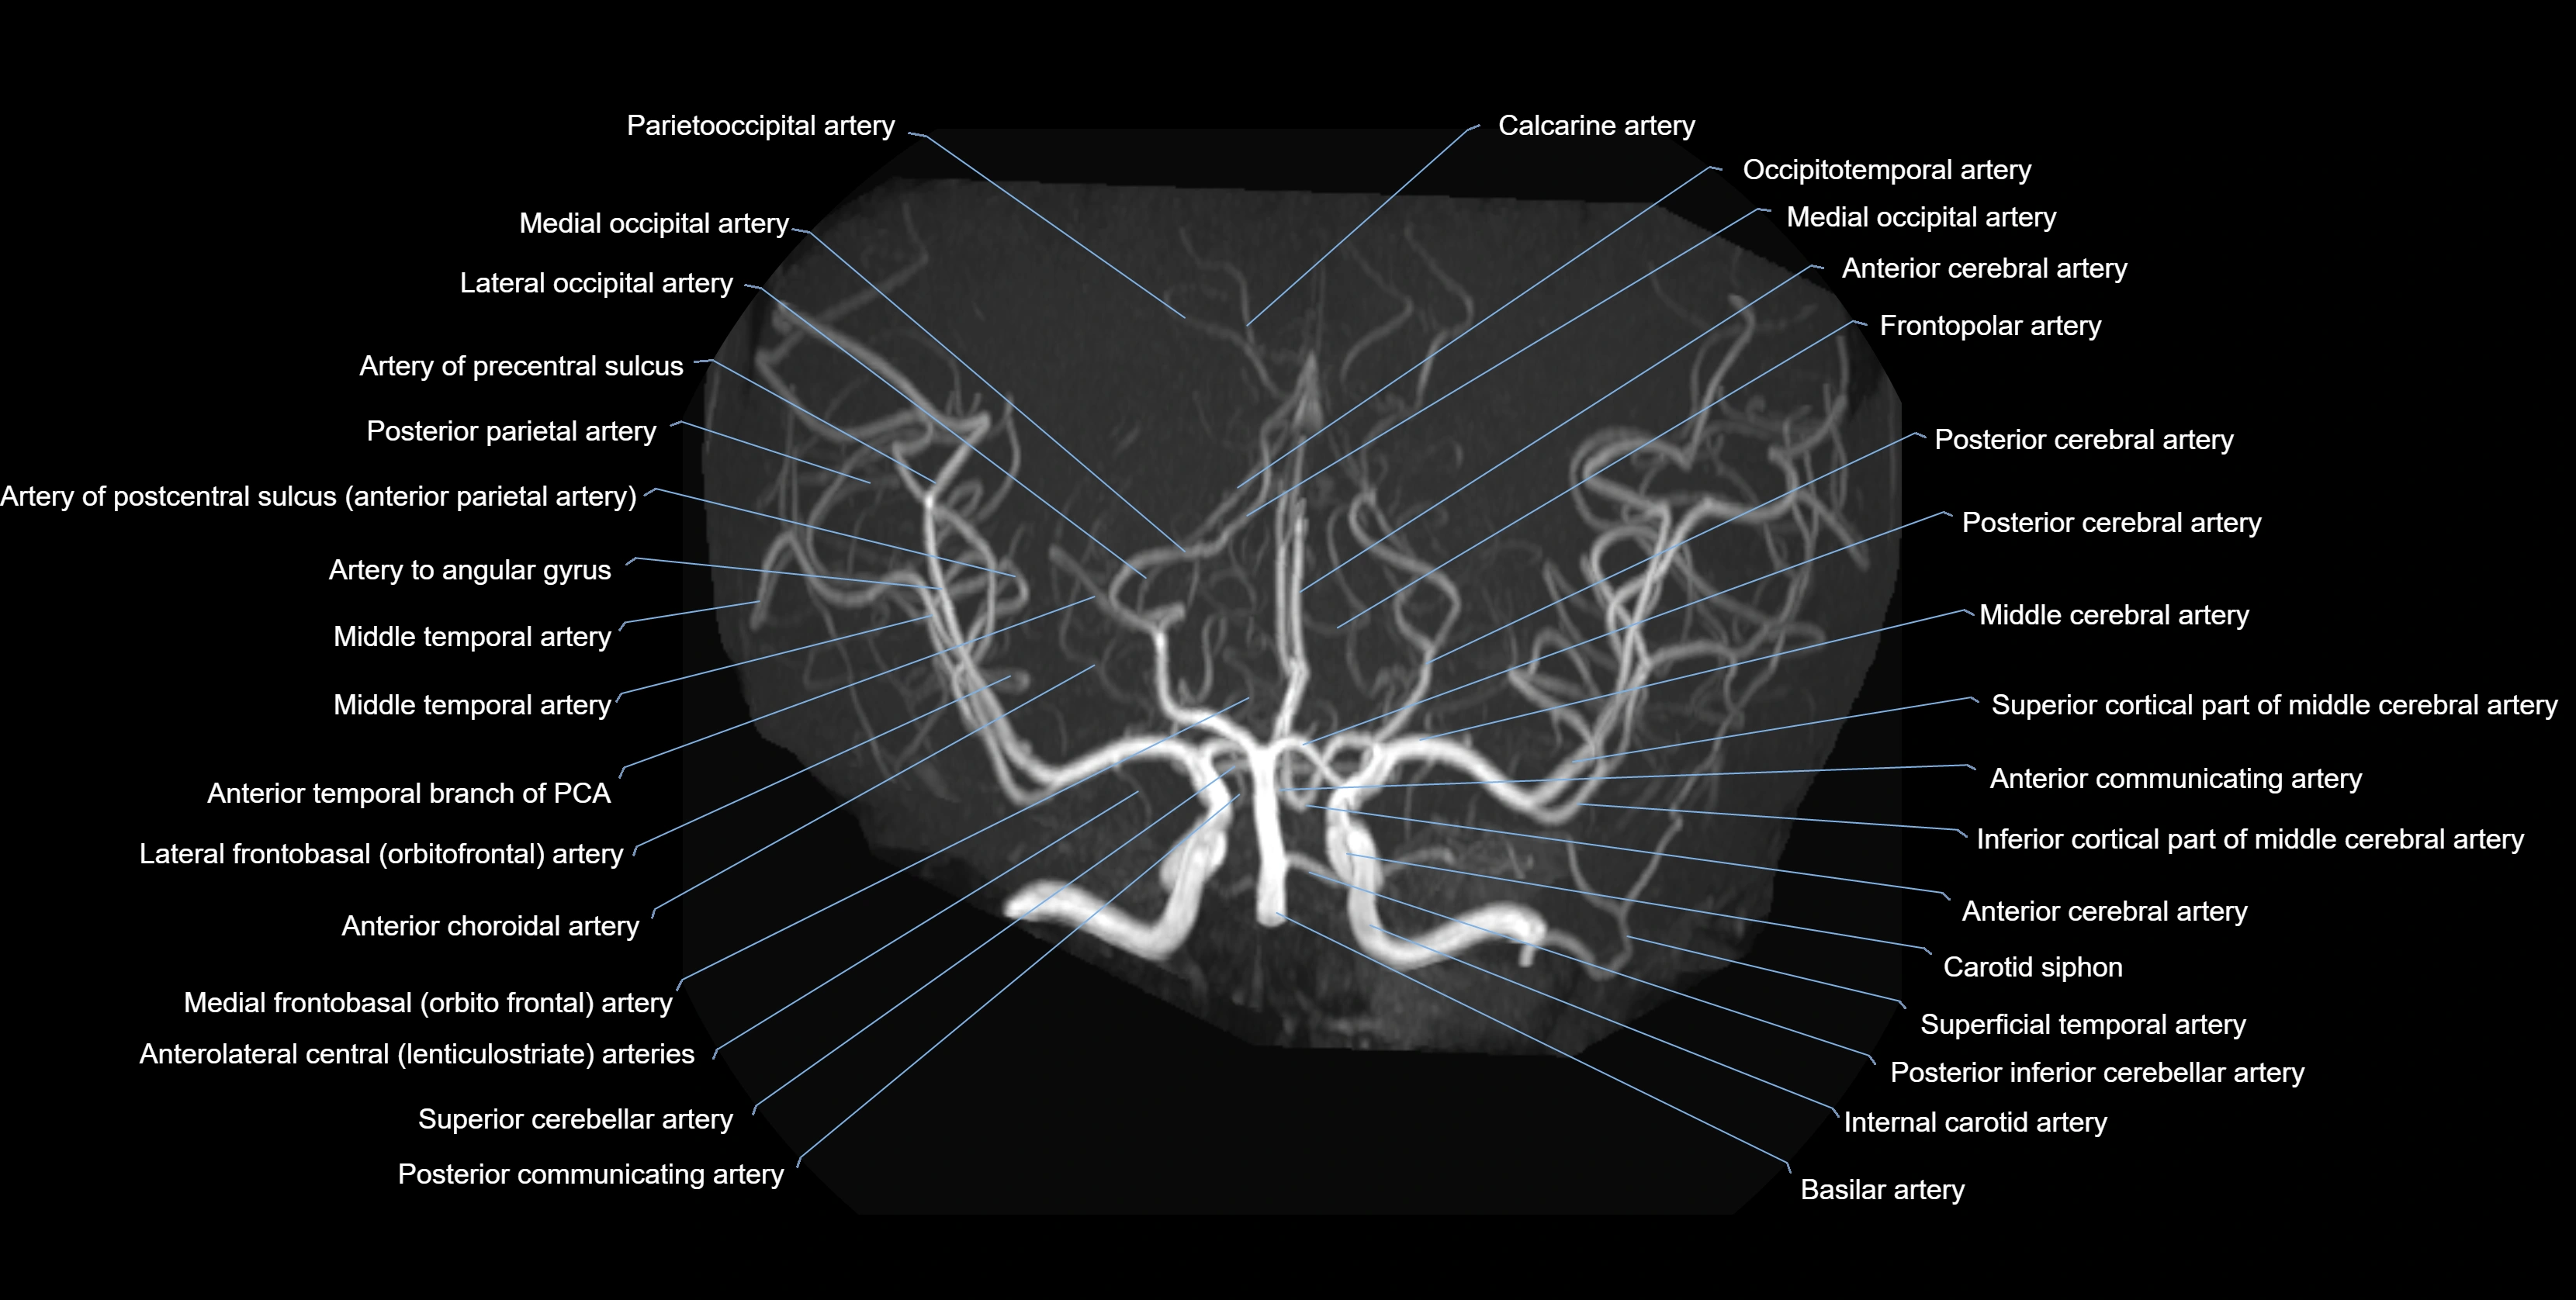

CTA (CT Angiography):

• Opacified with iodinated contrast, AChA appears as a bright high-attenuation vessel

• Visualized from ICA origin along optic tract toward choroid plexus

• 3D reconstructions depict its course and relation to adjacent arteries

• Gold standard for identifying aneurysms, occlusion, or vascular anomalies

CT images

image